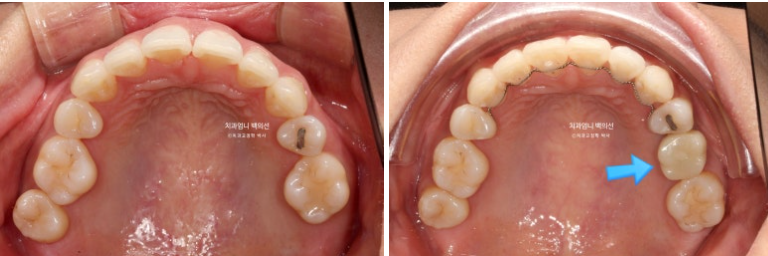

23.08

엑스레이상 좌측 위 첫번째 작은어금니 쪽으로 두번째 작은어금니가 쓰러지며 공간이 없어진게 보입니다.

23.08~25.06

파란 화살표 임플란트가 들어가고 좌우 치아갯수가 맞아졌습니다. 덕분에 중심선도 개선하고 어금니 교합관계도 1급이 되었으며 앞니가 뒤로 쓰러진 옥니도 고칠 수 있었습니다.